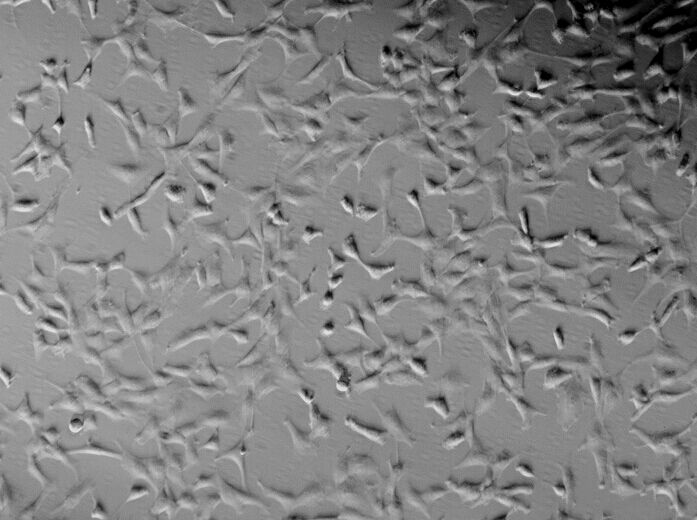

细胞形态:贴壁;上皮细胞样

5、 2-5分钟后,轻轻震荡培养皿。使H4人神经胶质瘤细胞从瓶壁脱离形成细胞悬液。显微镜下观察若细胞由贴壁变为悬浮就加入血清(即原培养液)终止消化。